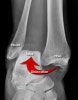

X-ray : 발목 관절 탈구(Ankle dislocation)

AP, lateral, Mortise view를 보면 대부분의 골절과 탈구가 진단됩니다.